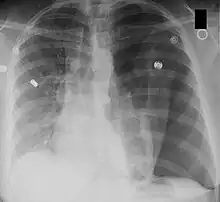

La radiographie du thorax de face permet de faire, en règle générale, le diagnostic, sous forme d'une clarté d'un sommet (ou péri hilaire dans les cas plus important) avec visualisation d'un fin liseré convexe vers le haut, correspondant au poumon rétracté. Dans les cas difficiles, on peut s'aider d'une radiographie prise en expiration. La présence simultanée d'un épanchement liquidien donne l'aspect de niveau hydro-aérique rectiligne horizontal caractéristique.